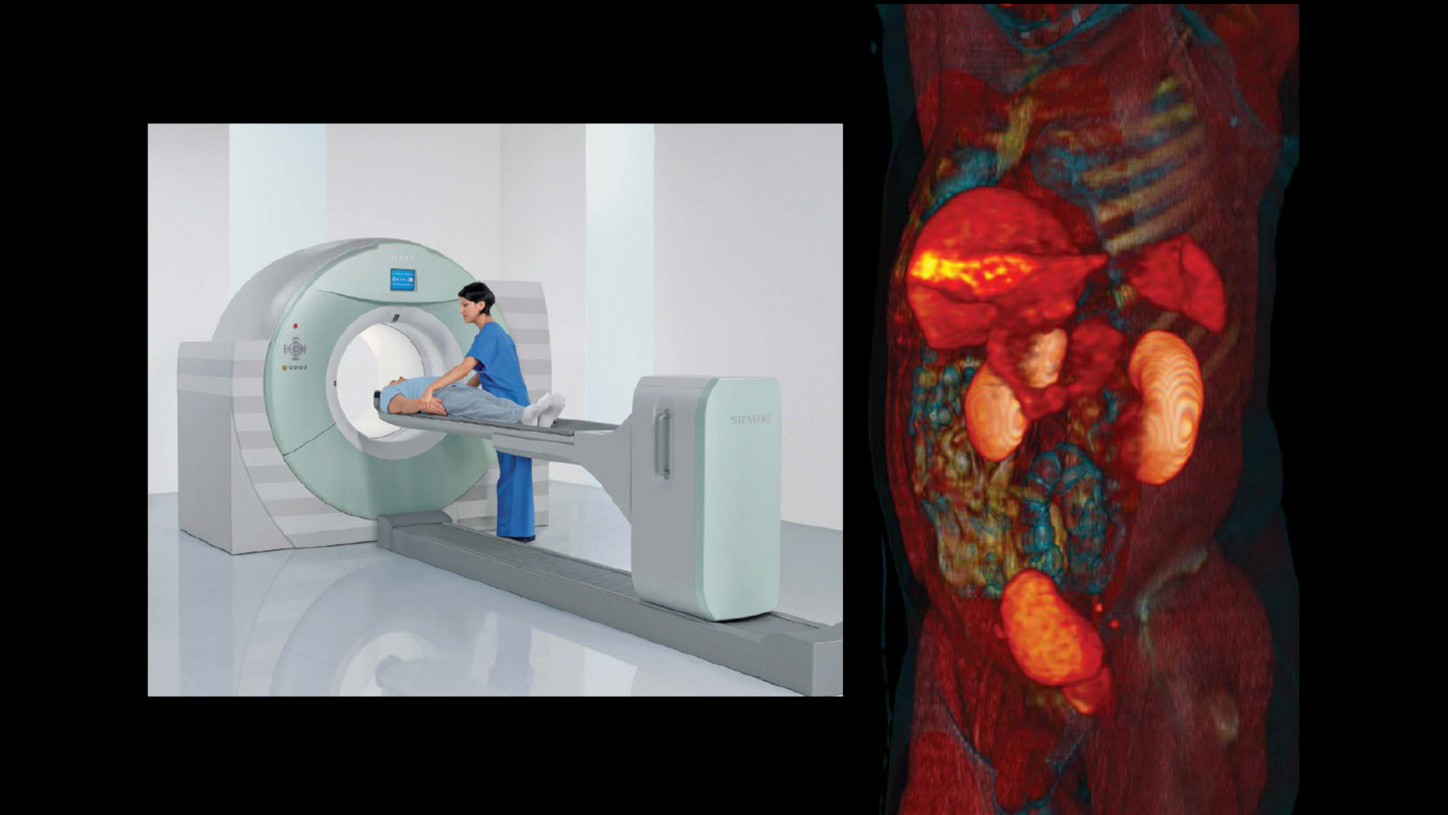

Biograph is the first commercial PET/CT system installed at the University of Pittsburgh Medical Center, Pittsburgh, Pennsylvania, USA. This system is revolutionary in that it combines PET and CT in a single diagnostic system. TIME magazine hails the PET/CT as “Medical Invention of the Year.”1

Biograph mCT is announced as the world’s first molecular computed tomography system and represents the evolution of integration in imaging. Biograph mCT is a combination of a state-of-the-art CT scanner with a high-performance PET system.

At the 1998 Society of Nuclear Medicine (SNM) annual meeting in Toronto, Canada, Townsend shared the first clinical PET/CT images with the world. Townsend looks back, “It was a very exciting time to be to be involved in nuclear medicine.” CTI and Siemens did not begin looking at the commercialization of PET/CT until about 1999, after enough clinical image data was acquired to convince physicians that it was a useful clinical concept.

The co-inventors, Townsend and Nutt, and members of the team remained involved in PET/CT’s development. In November 2000, the new scanner was unveiled to the world at the Radiological Society of North America’s (RSNA) annual meeting in Chicago, Illinois, USA. In December of the same year, the PET/ CT concept and prototype design was honored by TIME magazine as “Medical Invention of the Year.”1 By mid-2001, the first commercially available Siemens Biograph PET/CT system was installed at the University of Pittsburgh.